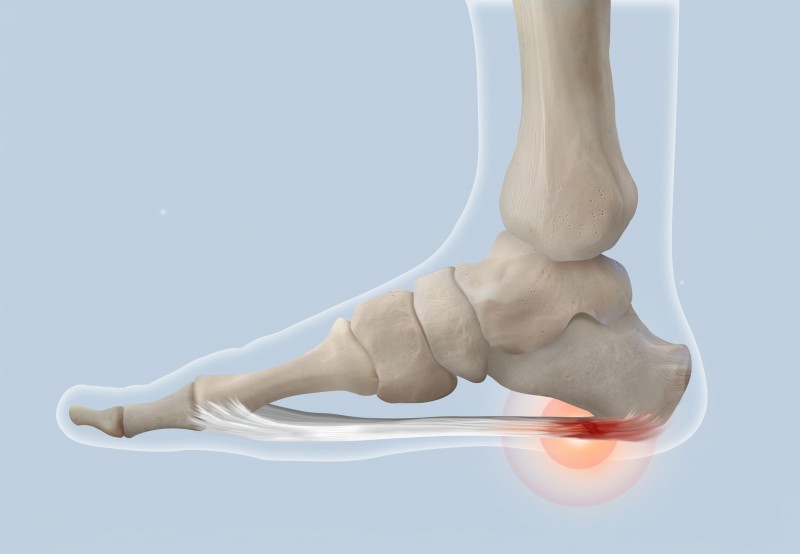

5. 족저근막염

발 아치가 무너지면 충격 흡수 기능이 저하되어 족저근막염이 발생할 수 있습니다. 아침에 처음 발을 디딜 때 극심한 통증이 특징입니다. 부산 평발교정 전문가의 도움을 받으면 족저근막염의 위험을 줄일 수 있습니다.